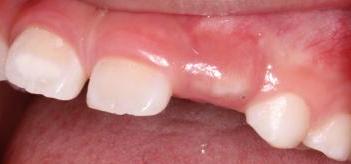

如果恒牙已经顶的牙龈已经发白了,还是长不出来,就需要到医院做一下助萌了。